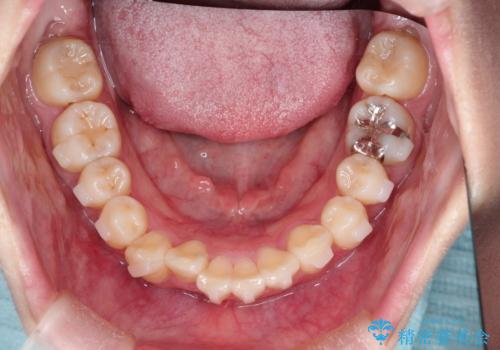

- 上下の前歯に捻れ(捻転)とガタつき(叢生)が見られます。

下の犬歯に関しても捻れと傾き、ガタつきが大きく、歯根の長さも相まって移動の難易度が高くなりがちです。

マウスピース枚数 初回33枚 +追加22枚 +追加31枚

概ね2年で治療完了しました。

マウスピース矯正の特性として動かすのが難しい歯を含むケースでしたが、当院独自の工夫を随所に盛り込み、狙い通りの治療結果が得られました。